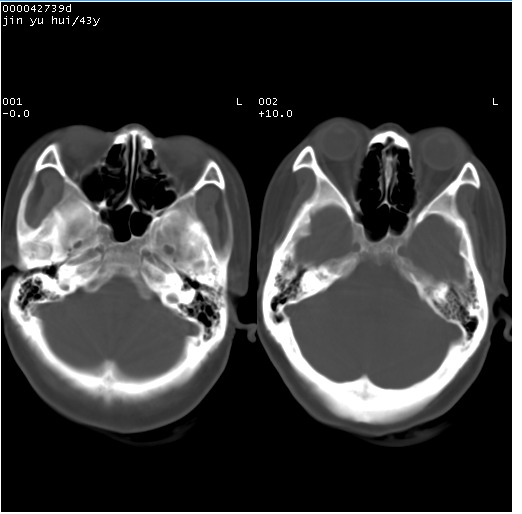

患者 女,43岁。头部外伤26天,经住院治疗,现头痛减轻。申请ct复查,了解颅内情况。

临床诊断:2级脑外伤。

颅脑ct轴位平扫(层厚、层距均为10mm),图像如下: